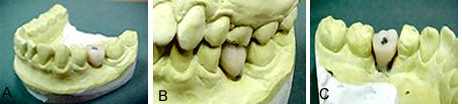

Figuras 8 a, b e c.

Figura 8a. São os modelos de trabalho, superior e inferior, para acerto de oclusão. No modelo inferior está construído o guia cirúrgico, que terá como vimos duas funções.

Primeiro realmente como guia na cirurgia e em seguida como transferente do implante para o modelo de trabalho, assim, o modelo de estudo e confecção de guia, servirá também, como veremos de modelo de trabalho para a confecção da coroa a ser colocada, sobre o implante.

Figura 8b. São as peças que compõem os “abutmans” do sistema Conect a ser usados para confecção da coroa.

Figura 8c. Mostra o guia cirúrgico colocado na posição, para fixação do monta implante, que foi recolocado como mostramos na figura 8a e b ao guia, para servir de transferente para o modelo de trabalho. Essa fixação, deve ser cuidadosa, usando-se para isto resina de autopolimerização, pois o parafuso de fixação não deve ser envolvido de resina, caso contrário a peça não poderia ser mais removida.